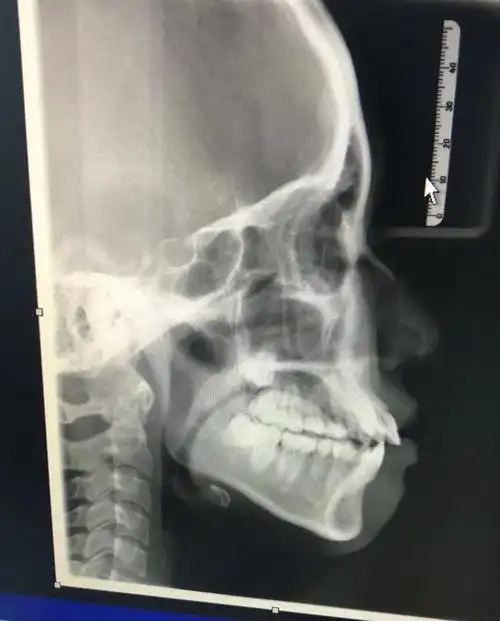

初诊时无论是侧貌,x光片都存在前突,牙齿唇倾的问题

牙片八个月的侧脸差距

/strong> /p> p>牙片,是牙齿的x线片,口腔科常用的检查

牙齿x光,也就是牙科x射线摄影,是一种通过x射线透视牙齿和颌骨的际貂

通过x光片可以了解牙齿病变情况,了解牙槽

这种侧面带牙套有用吗是不是只能正颌手术了03新加了牙齿拍片图

拍到,它的优点是可以展现出整个口腔里的牙齿及口腔周边解剖结构颌骨

由正畸医师进行临床资料的采集,拍口腔全景x光片,还有面部,牙齿和口腔